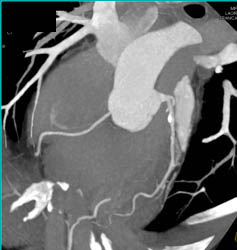

Vessel Analysis to Determine Plaque Composition